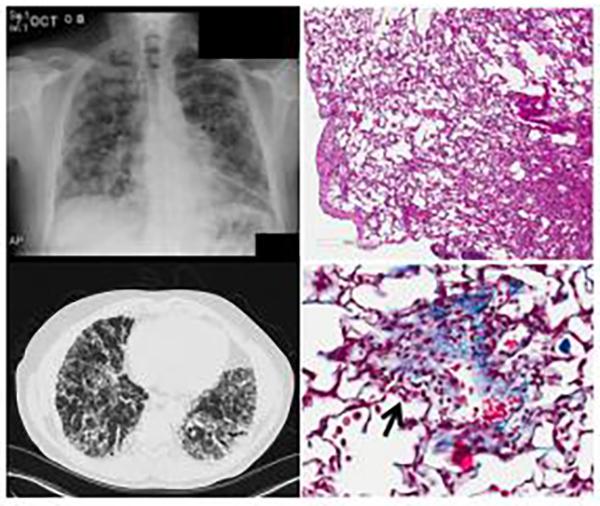

CTSC Pilot Award Fuels Breakthrough in Sustained-Release Therapy for Pulmonary Fibrosis

This 2021 CTSC Annual Pilot Award study highlights the power of interdisciplinary collaboration. CWRU PhD candidate, Emmanuel Einyat Opolot and colleagues found that polymer microparticles can deliver the antifibrotic drug Nintedanib more effectively, reducing both dosing frequency and inflammation in a mouse model of idiopathic pulmonary fibrosis (IPF). Co-author, Amar Desai, PhD, shares, “The CTSC Pilot Award enabled us to collaborate and develop novel sustained-release strategies—our latest work shows that this approach may offer a safer, more durable way to deliver medicines for chronic lung disease.”

CTSC Leadership Drives Innovation in IPF Therapy

Dr. Amar Desai, incoming co-lead to the CTSC pilot module, is the senior author of a new study developing beta-cyclodextrin polymer microparticles for sustained Nintedanib delivery. In a mouse model of idiopathic pulmonary fibrosis, this approach maintained drug levels for over 70 hours, reduced inflammation, and minimized dosing.